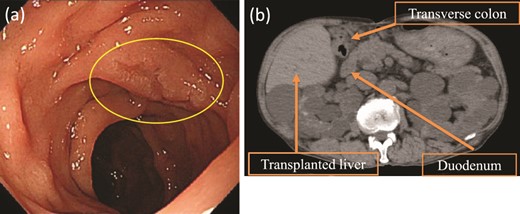

Upper gastrointestinal endoscopy revealed a high-grade adenoma by biopsy, 15 mm in diameter, on the opposite side of the ampulla of Vater (Fig. 1a), and we decided to perform D-LECS. Preoperative computed tomography (CT) revealed no metastasis to any other organs but that the transplanted liver was very close to the transverse colon (Fig. 1b). Moreover, strong adhesions around the liver were expected because of bile duct anastomotic leakage after LDLT. To avoid damage to the vital liver and transverse colon, we first considered to dissect the mesentery of the transverse colon before an approach from the anterior surface of the pancreatic head to the second portion of the duodenum to create an adequate space for surgery.

Upper gastrointestinal endoscopy and abdominal plain CT findings. (a) Upper gastrointestinal endoscopy showing the elevated lesion (10 mm in diameter) at the opposite side of the ampulla of Vater. (b) CT showing the transplanted liver very close to the transverse colon (axial image).